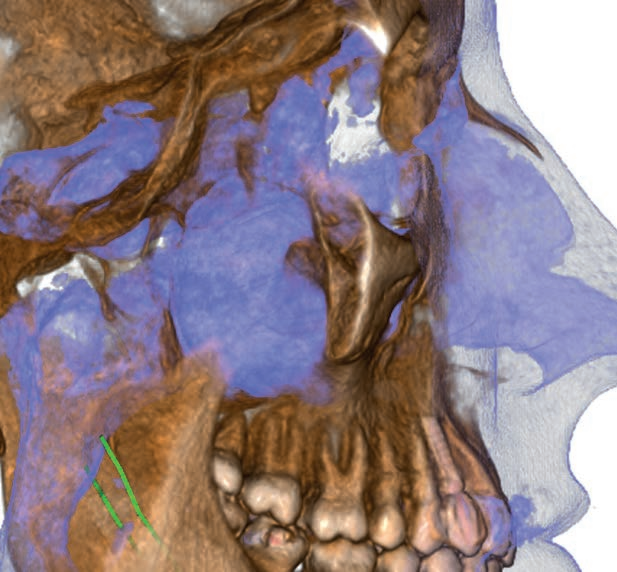

Hyperion X5全景、头颅和X射线体层摄影设备

Hyperion X5不断进化发展,现在头颅及3D拍摄也来到您的面前。这边在整个拍摄过程中快速易用,确保了高分辨率的3D和2D图像、低辐射时间以及实时诊断所需的快速数据处理,改善医患沟通。新的虚拟控制面板简化了拍摄流程,并引入了上颌窦容积检查和正交全景图像的新程序。由于3D传感器模块的自动伺服控制运动,较短的检查时间确保了连续的愉快体验。